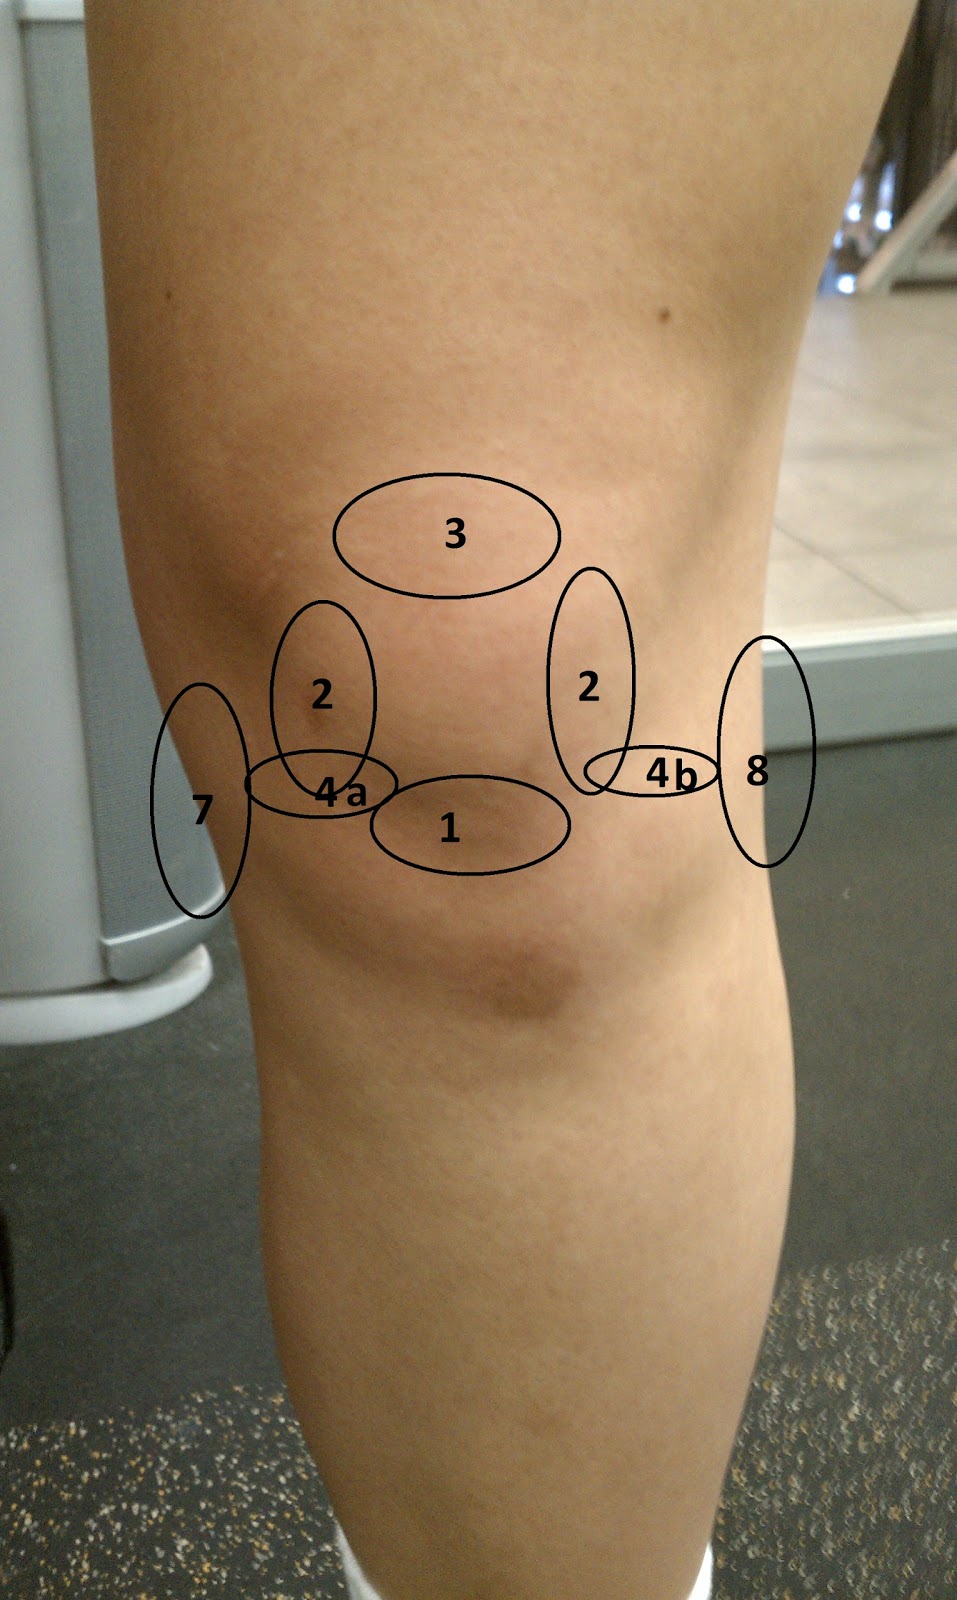

Возможные причины болей в ноге ниже колена и рекомендации